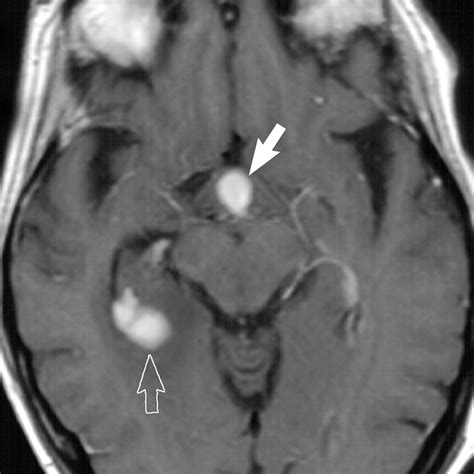

• Pituitary tumors: Tumors in the pituitary gland can compress the infundibular stalk, leading to hormonal imbalances and neurological symptoms.

• Vascular events: Conditions such as pituitary apoplexy, which involves the sudden hemorrhage or infarction of the pituitary gland, can affect the infundibular stalk.

• Imaging studies: Magnetic resonance imaging (MRI) is the gold standard for visualizing the pituitary gland and the infundibular stalk. It can detect tumors, inflammation, and other structural abnormalities.